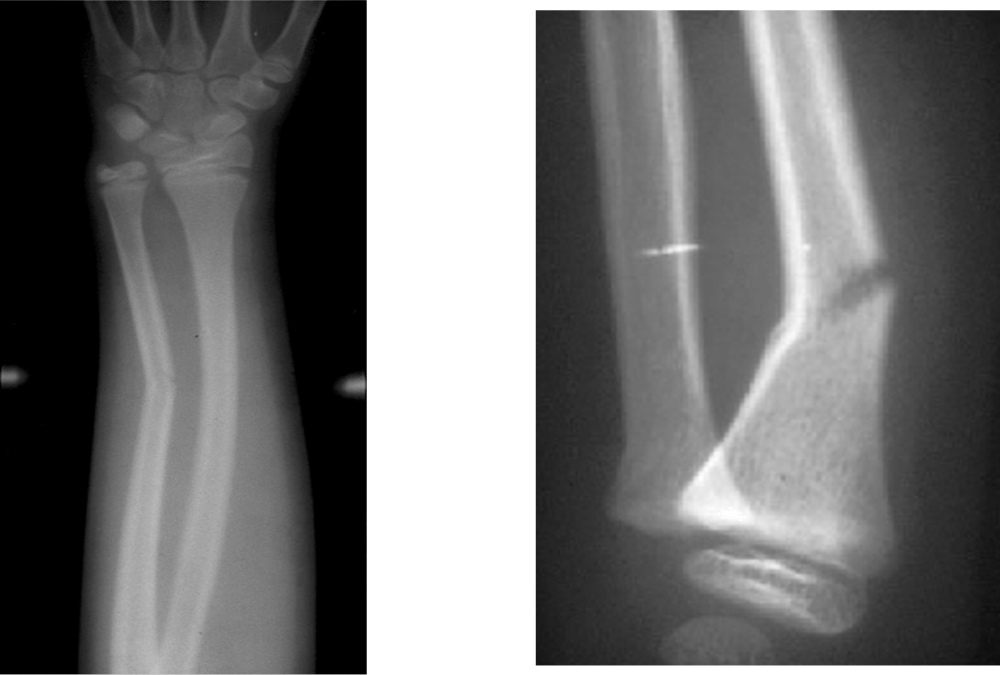

A type III fracture (see the images below) is a fracture through the physis and epiphysis. This fracture passes through the hypertrophic layer of the physis and extends to split the epiphysis, inevitably damaging the reproductive layer of the physis.

A type II Salter-Harris fracture is the most common pediatric physeal fracture, occurring frequently in children over 10 years of age. This fracture breaks at an angle, cutting through most of the growth plate and the metaphysis, the area above the growth plate.